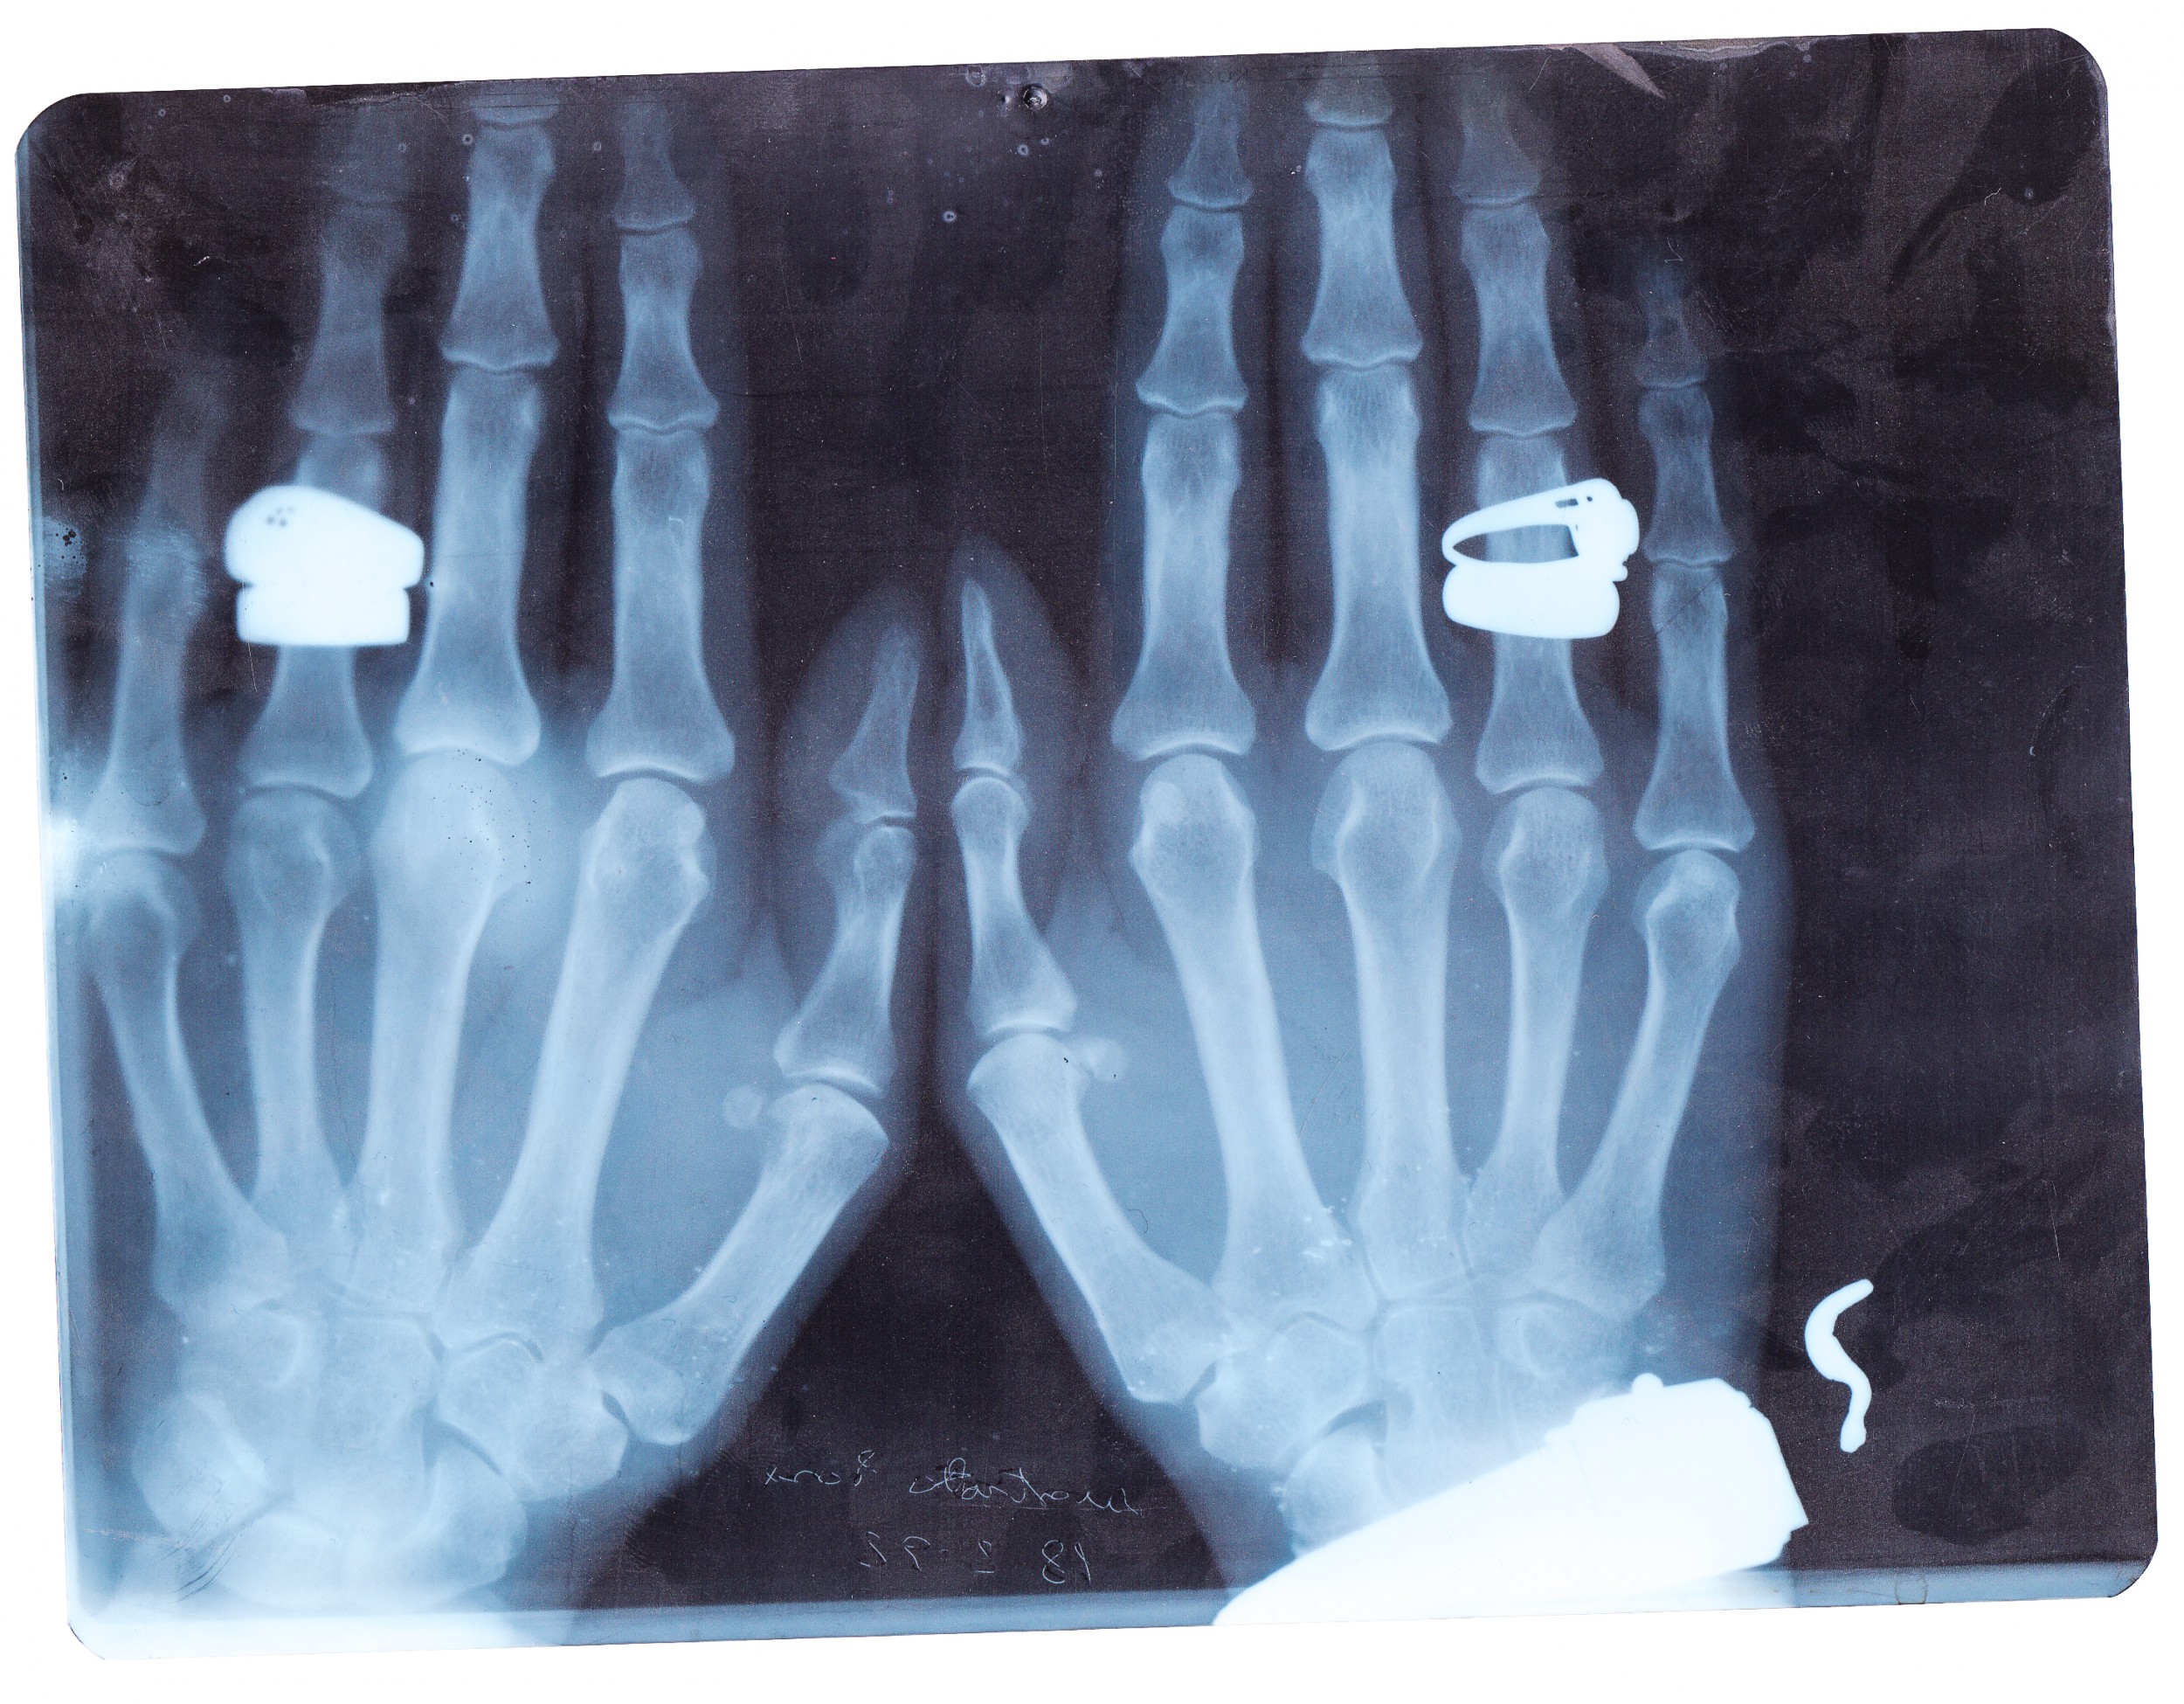

Il recupero di radiografie appartenute a un ortopedico attivo negli anni '80, permettono un'incursione attraverso il tema dell'errore, degli spazi del discorso nell'immagine e dello slittamento del senso.

La dislocazione produce delle opere simili ai rayogrammi di Man Ray o agli equivalenti di Stieglitz, continuando allo stesso tempo a parlarci della pratica vernacolare.